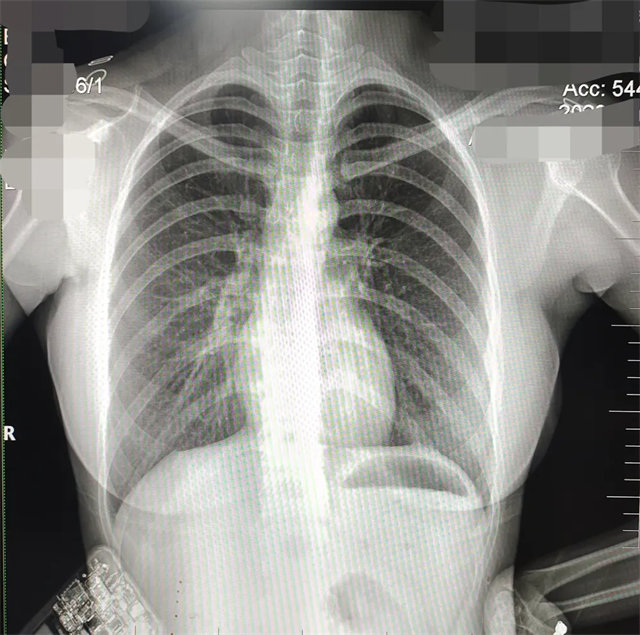

缺陷:兩肩胛骨未拉開肺野之外,吸氣不完全,且存在金屬飾品遮擋。

解決:去除金屬飾品及內(nèi)衣后重新按標(biāo)準(zhǔn)體位攝片即可。